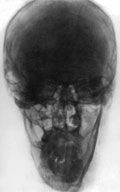

Телерентгеннограмма в прямой и боковой проекциях. Сочетанная деформация лицевого черепа, синдром «длинного лица».